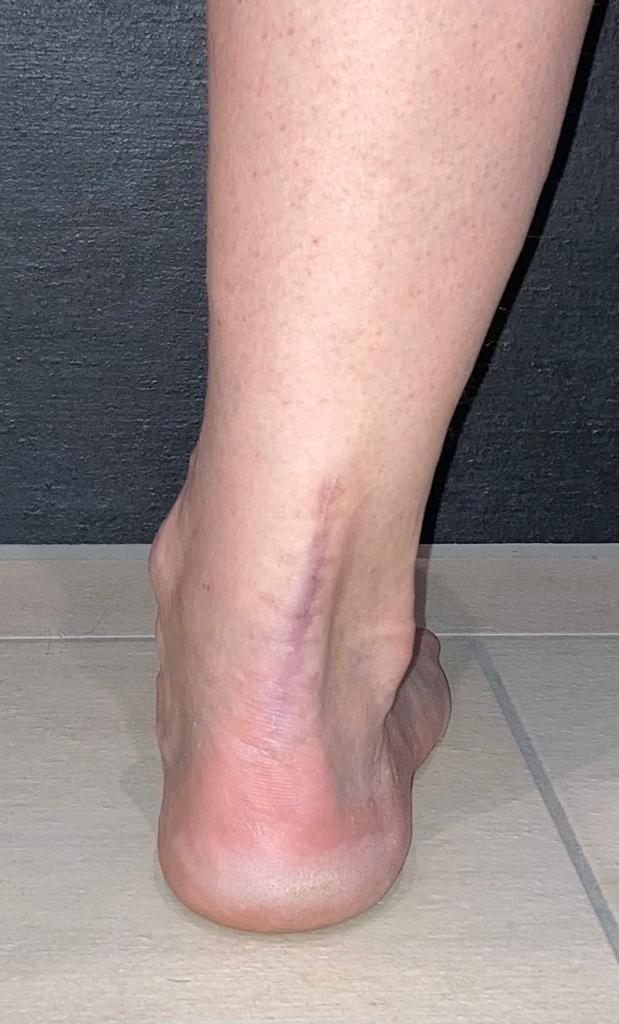

Von „geringeren“ Wadenmuskeln bzw. -umfang kann bei mir keine Rede sein:

Zumindest auf dem Foto schaut der Wadenmuskel mit der Achilles OP, schon etwas schmäler aus, als der gesunde...

Ich finde auch, dass man auf dem Bild zumindest optisch einen recht grossen Unterschied sehen kann. Bei mir, mittlerweile 10 Jahre her, hat sich die Differenz auch nie mehr ausgeglichen, merke aber überhaupt nichts davon.

Jetzt habt Ihr mich aber neugierig gemacht, Ihr Adleraugen!

Also links 46 cm und rechts 44,6 cm.

Also tatsächlich ein Unterschied von 1,4 cm.

Ich weiß natürlich nicht, ob beide Waden vor dem Achillessehnenriss auch den gleichen Umfang hatten.